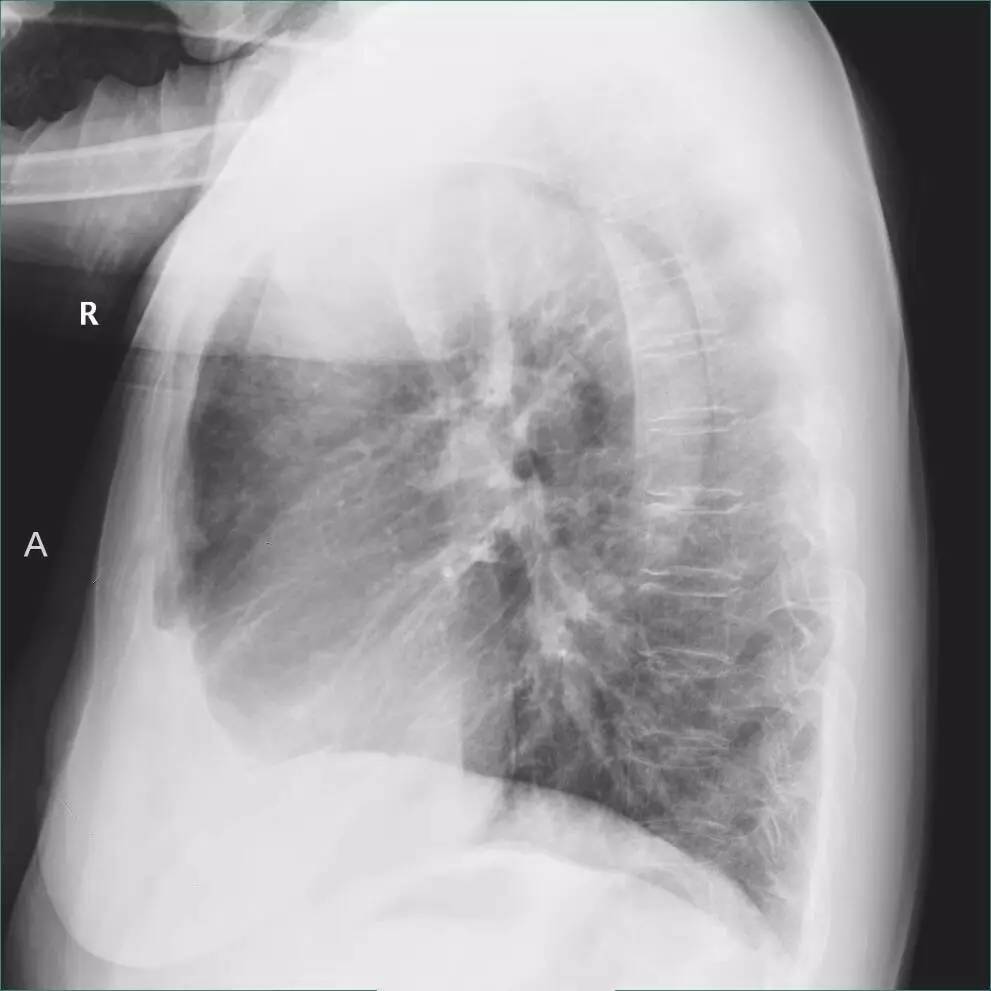

>>>>病例3:女,89岁,慢阻肺多年。

左侧胸腔最有可能的诊断是?

A.包裹性积液

B.胸膜增厚

C.胸腔积液

D.心包脂肪垫